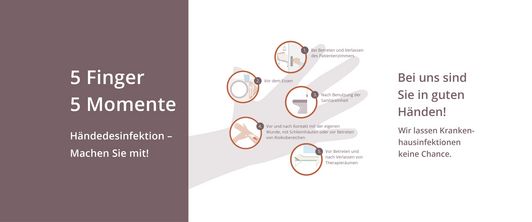

Mit unserem Aktionstag "Saubere Hände"! An diesem Tag möchten wir sowohl unsere Mitarbeiter als auch unsere Patienten für die Bedeutung der Handdesinfektion sensibilisieren.

Aktionstage "Saubere Hände" in unseren Kliniken für Mitarbeiter und Patienten